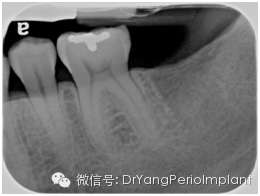

达到诊断质量的根尖片(X光片取自笔者治疗过的病人)。

诊断质量欠佳的根尖片(原因:显示太多occlusal table说明片子有变形) X光片取自笔者治疗过的病人)。

根尖片上看什么呢?

1. 骨量(bone level): (AAP 2015--Task Force Report,见美国牙周协会American Association of Periodontology 网页:https://www.perio.org/resources-products/clinical-scientific-papers.html

1有骨缺失(no bone loss)

2水平骨吸收(horizontal bone loss)

轻度:<15% 牙根长度,2-3 mm,

中度:16-30%, 3-5mm,

重度:> 30%, >5 mm

3垂直骨吸收(vertical bone loss) (1-, 2-, 3-壁牙周袋, 骨吸收占牙根长度比例)

2. 冠根比例(crown root ratio) (有利,可接受,不利的划分以1:1为界限)

3.牙周韧带宽度(Periodontal ligament width)(正常宽度大约0.2 mm

4. X线片上有无可见牙石(radiographically visible calculus)

5. 牙根形态 (root morphology): 锥形,柱形,长度,与临牙牙根关系

6. 根尖阴影(periapical radiolucency ) (+/-), 牙根吸收/合并/弯曲/多生牙根

7. 根干长度(root trunk length):

(3 mm)中等(4 mm), (5mm)—上颌

(2 mm)中等(3mm), (4 mm)—下颌

8. 根分叉阴影 (furcation radiolucency) (+/-)

9. 根分叉入口 (furcation entrance):根分叉箭头 (高度特异性)

10. 磨牙牙根分离度/融合度(root separation/fusion)

11. 牙槽骨硬板(lamina dura)

12. 临牙间牙釉质牙骨质分界差异(CEJ discrepancy)

13. 牙槽骨松质骨,病理变化 (cancellous bone and/or pathological changes)

14. 任何修复体(restoration)(是否有悬突,修复体边缘是否密合,修复体边缘是否侵犯生物宽度,边缘脊是否一致)